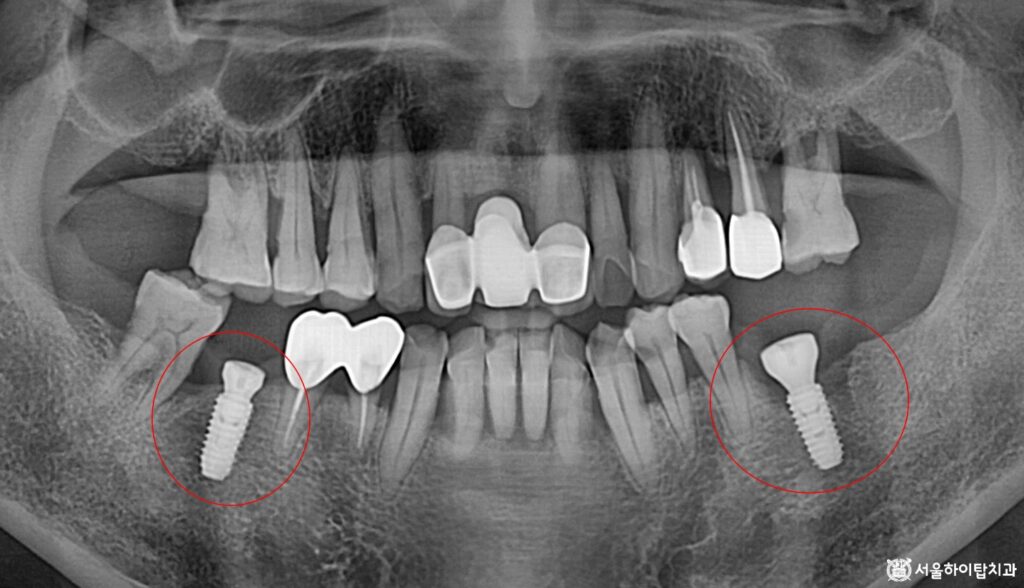

시뮬레이션 데이터에 따라

정확한 위치에 안정하게

픽스처가 심겨진 모습입니다.

당일 식립이 이루어졌기 때문에,

한 번의 시술로 기능을 회복할 수 있고,

치유 기간도 단축되어

빠른 회복이 기대됩니다.

또한, 장기간 상실된 부위와

치주염으로 인해 손상된 뼈를

동시에 관리할 수 있어,

교합 안정과 심미적 회복도

동시에 도모할 수 있습니다.

이후 약 3개월 동안은 주변 뼈와 픽스처가

결합되는 골유착 과정을 거치게 됩니다.